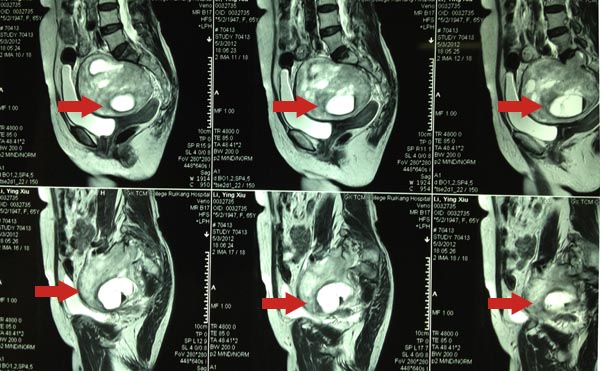

• 巨大神经鞘瘤被成功切除

巨大神经鞘瘤被成功切除

2012年4月28日,广西中医药大学附属瑞康医院脊柱一区来了位广西桂林的女性老年患者,患者及家人诉3个月前曾于一次偶然的体检,发现了盆腔内长...

发布时间:2012-05-16 来源: